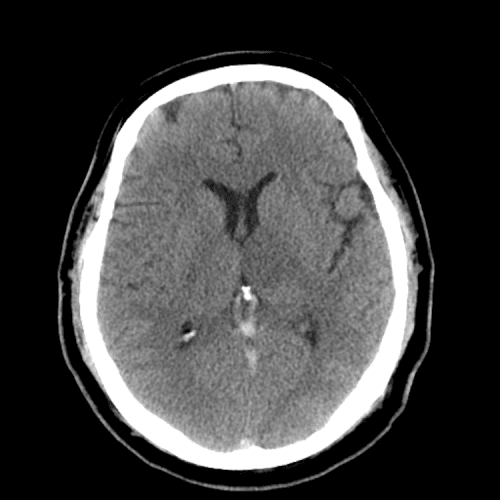

ACA and MCA territory infarct